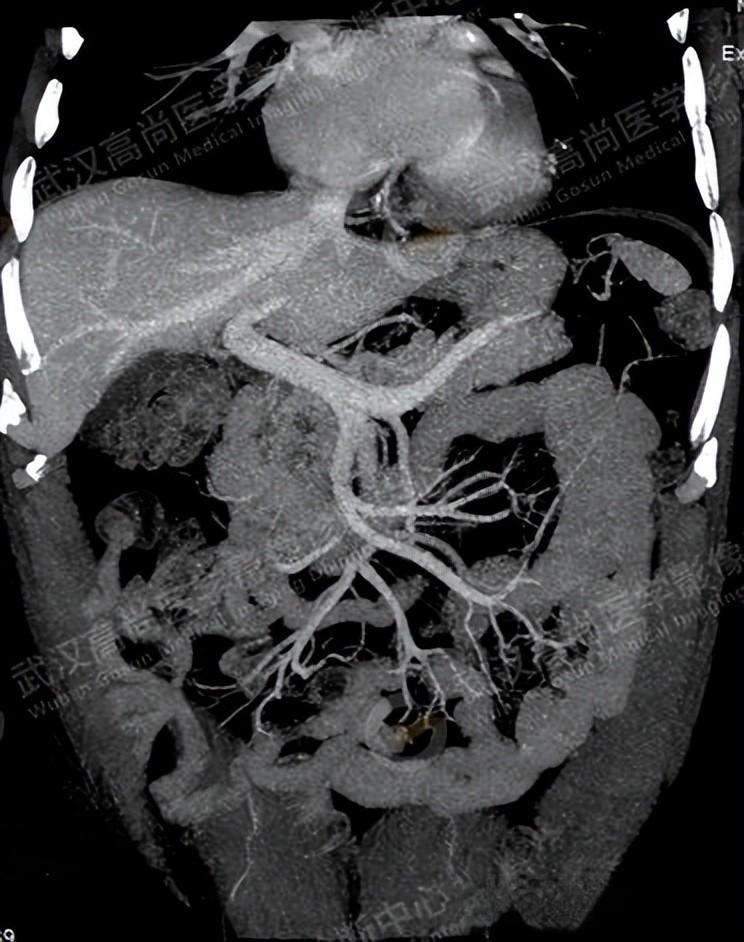

在LSPH的诊断中,CT因其全面性和准确性而成为目前应用最为广泛的方法。CT可以清晰显示原发病灶、脾静脉及其病变、静脉曲张、脾肿大以及肝脏及肝门静脉是否正常。通过CT增强+血管成像,可以观察到脾静脉狭窄、胃短静脉曲张、胃底静脉曲张、胃冠状静脉扩张等特征性表现。例如,在一例慢性胰腺炎急性发作的患者中,CT增强+血管成像显示脾静脉狭窄,脾门及胃网膜静脉曲张,脾-肾静脉分流,而肝门静脉及肠系膜上静脉正常。